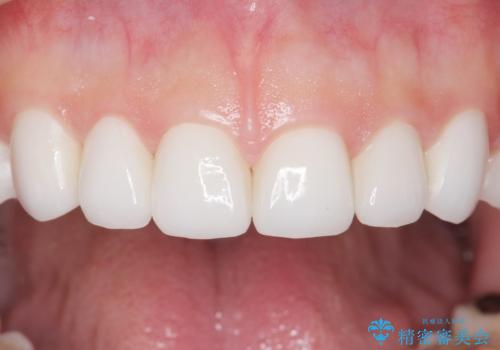

綺麗な仕上がりにご満足下さいました。

奥歯の咬み合わせも良くなったと喜んで頂けました。

患者様の理想とする韓流アイドルの写真を技工士さんに送り、最終的なクラウンの形や色をできるだけ理想に近づけられるよう努めました。

下顎はホワイトニングを行っております。